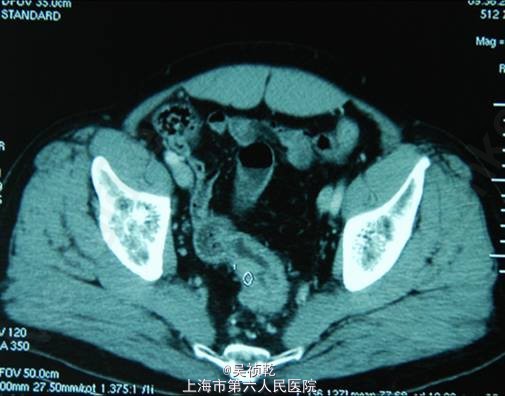

查体:浅表淋巴结(-)既往无重大疾病,体重下降5kg,肿瘤CEA>1500 ug/L。胸部CT :左下肺占位,考虑转移。上腹部CT :肝脏多发转移。盆腔CT :直肠肿物,伴不全肠梗阻。

术前诊断:直肠癌伴肝肺转移(肝脏多发,肺单发) 行直肠癌TME手术:术中探查:肝脏多发转移结节,最大者4cm, 无腹水及腹盆腔种植结节; 直肠肿瘤距肛门8cm,侵犯浆膜外脂肪组织。 病理:溃疡型管状腺癌II级,4.5*3.5*2cm,侵至肠壁全层,达肠周脂肪组织,肠周淋巴结转移: 6/12,肠系膜动脉根部0/2淋巴管(+)神经周围(+)血管(+)。K-ras检测:野生型 术后行化疗方案为:FOLFOX 4+Cetuximab (q2wk * 6次) 后评估肿瘤部分缓解,6次化疗结束后改为XELOX / q3wk*6次,评估肿瘤无进展。 下图可见复查的影响学资料相比化疗前肿瘤有明显缩小。